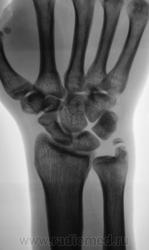

Перелом шиловидного отростка локтевой кости? Или я чего-то еще не замечаю?

Без костно-травматических изменений. В данном случае либо неслияние ядра окостенения ш. отростка, либо б-нь Мюллера, тут уж клиницист должен д/д проводить.

Поддержу не слияние, клиника травмы значит в пользу Мюллера данные вряд ли будут.

Без видимых костных повреждений; вариант окостенения шиловидного отростка локтевой кости.